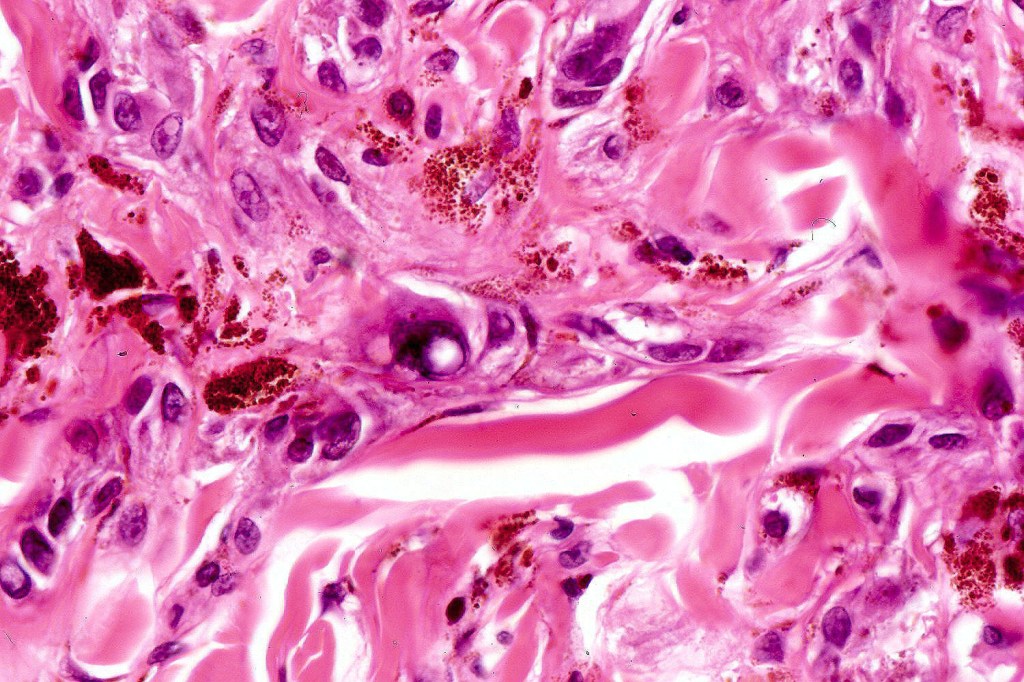

Cellular blue nevus

Histological features

•Most characteristic is the dumbbell silhouette although a plague morphology may also be encountered

•Combined nevus variant

•Admixture of spindle cells, pigmented bipolar or dendritic cells & melanophages

•Cytoplasm is pale and nuclei are small with inconspicuous nucleoli

•An alveolar pattern is characteristic particularly with clear cell nodules

•Mitoses are typically very sparse or absent

•No atypical mitoses

•No Necrosis or lymphovascular invasion

•Multinucleate giant cells sometimes present

•Stromal fibrosis, myxoid change, vascular hyalinization with cyst formation are often seen

•Some tumors are composed spindle cells in a fascicular or neuronevoid pattern

•Perineural involvement may be seen

•Balloon cell change

•Desmoplastic variant

•Hypopigmented variant